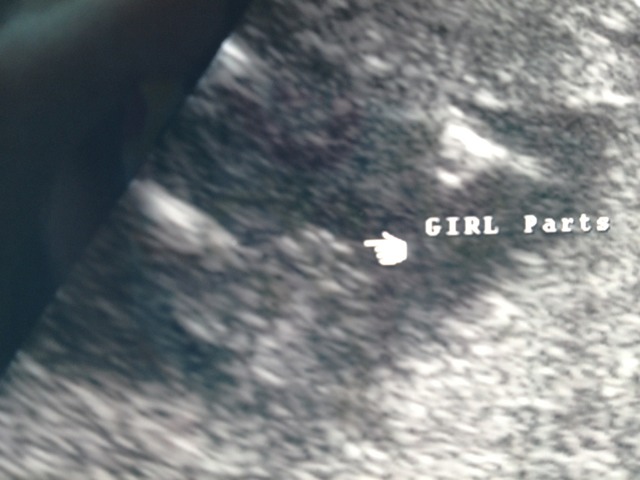

Tech was very confident. Looks girly to me but would love other opinions?? Here are two different views.